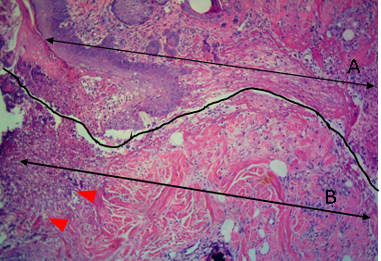

Histological section of autograft site of dog’s leg after one week of surgery. Showed two sides of the tissue, the original tissue showed no signs of rejection (A), while the grafted tissue (B) showed necrosis and degeneration of the dermis layer (arrowhead). H&E, 100x.